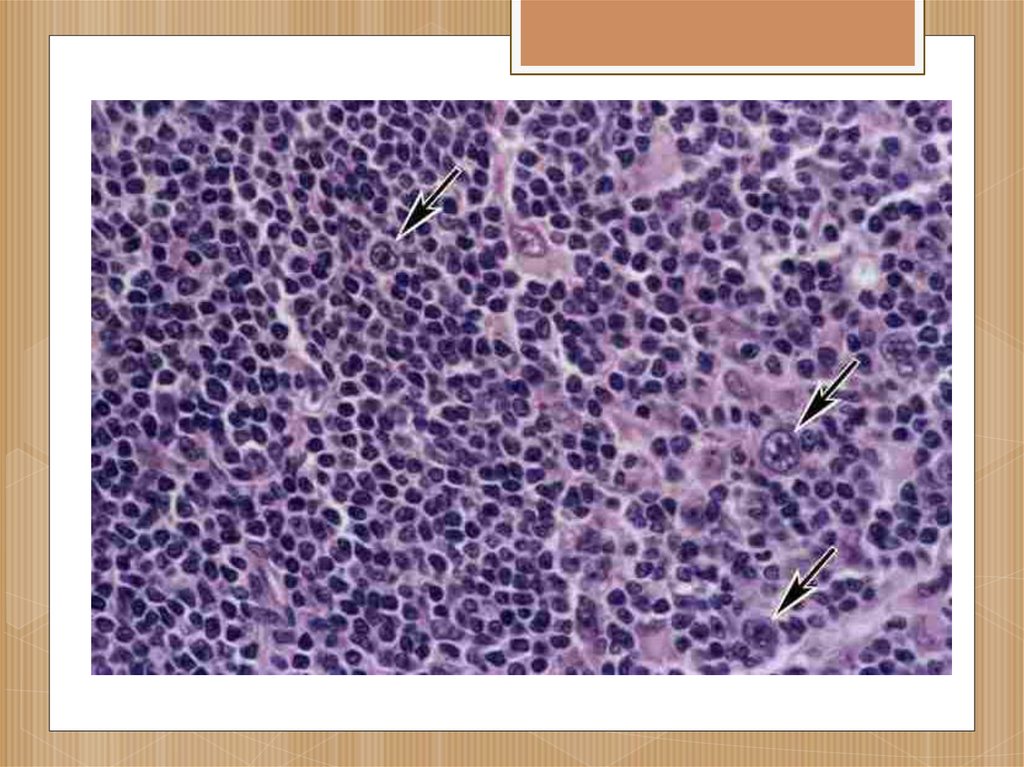

Микропрепараты: Лимфогранулематоз и Нодулярный Склероз

Раздел: Секреты мастерства